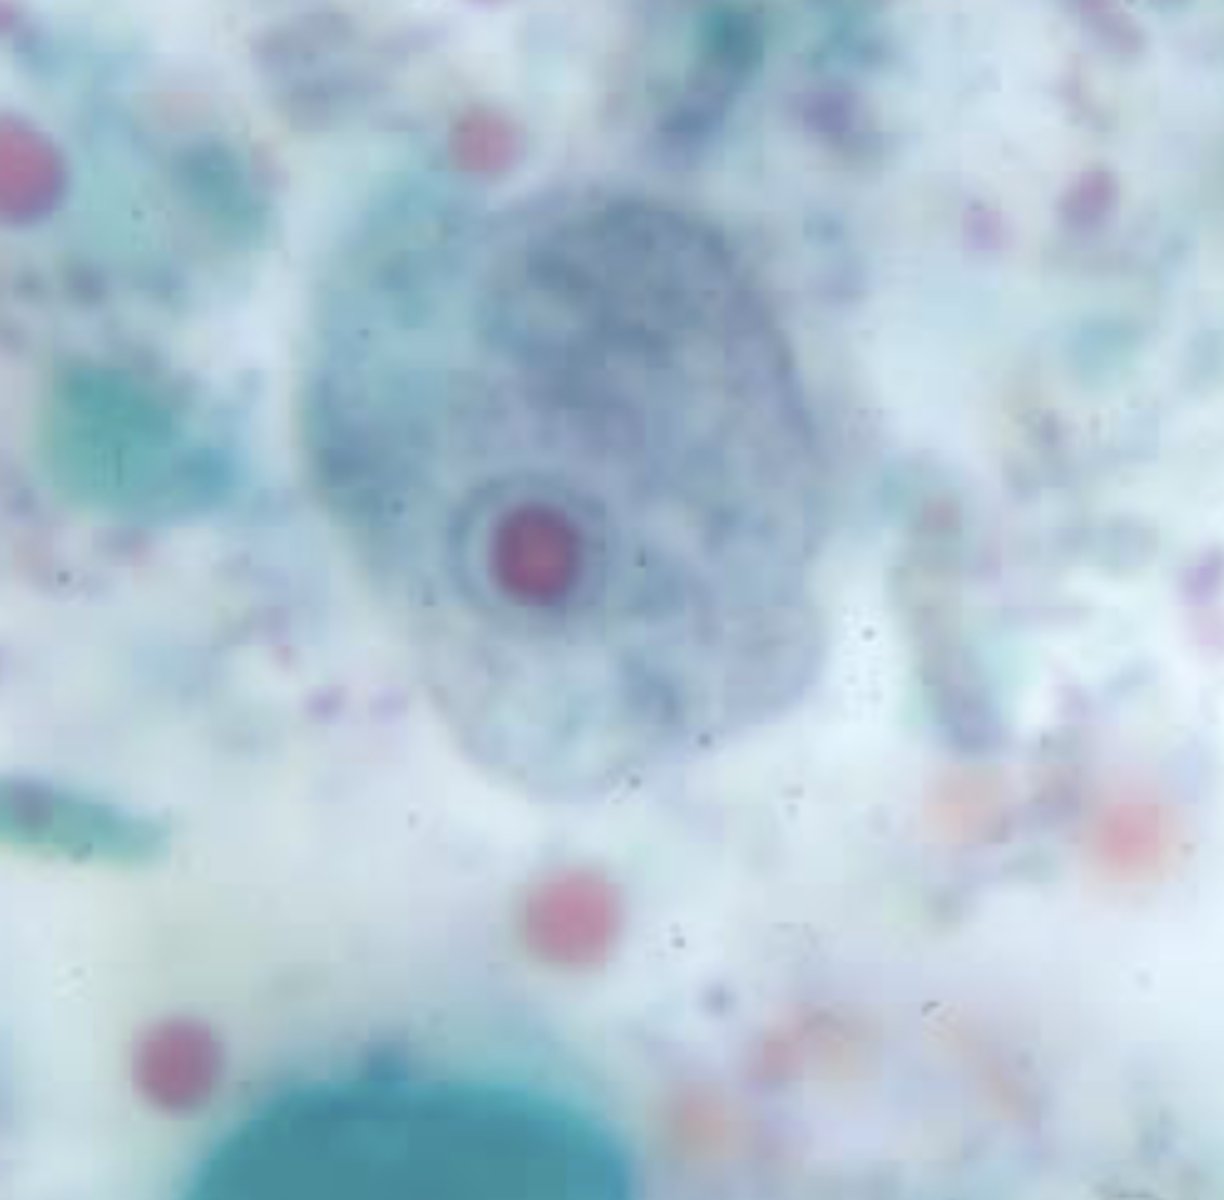

Entamoeba histolytica troph, ingested rbc

Entamoeba histolytica/dispar troph

10-60 um